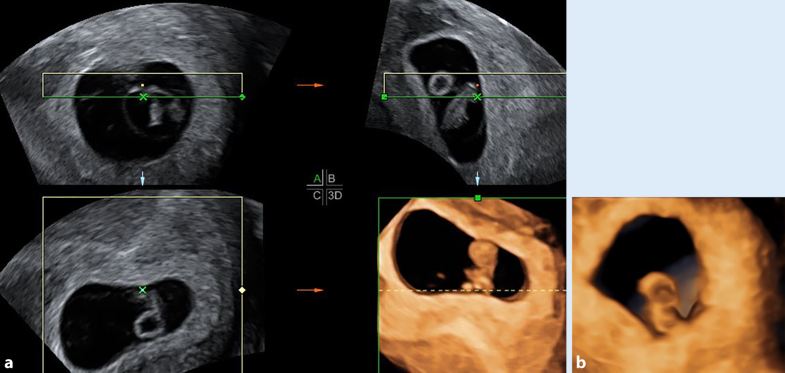

Warum ist die 6. SSW so wichtig? Weil man in dieser Woche oft zum ersten Mal im Ultraschall sowohl die Fruchthöhle als auch den Dottersack sehen kann. Und das ist ein super Zeichen! Es bedeutet, dass sich die Schwangerschaft ganz normal entwickelt. Natürlich ist jede Frau und jede Schwangerschaft anders, aber wenn dein Arzt oder deine Ärztin in der 6. SSW beides sieht, dann kannst du erstmal erleichtert aufatmen. Stell dir vor, es ist wie beim Führerschein: Fruchthöhle und Dottersack sind die bestandene Theorieprüfung! Jetzt kommt die Praxis, aber die Grundlagen stimmen schon mal.

Wenn dein Arzt oder deine Ärztin sagt: "Alles super, Fruchthöhle und Dottersack sind da, und sie sehen gut aus!", dann kannst du innerlich schon mal die Korken knallen lassen (natürlich alkoholfrei!). Ein "gutes Zeichen" bedeutet, dass die Größe der Fruchthöhle und des Dottersacks altersgerecht sind. Stell dir vor, es ist wie beim Bäumchen pflanzen: Wenn der Setzling eine ordentliche Größe hat und gut im Boden steht, dann sind die Chancen groß, dass er prächtig wächst und gedeiht.